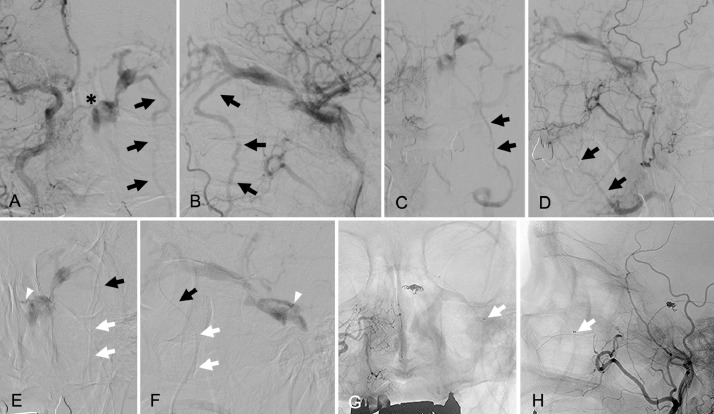

A 66-year-old woman who presented with left-sided chemosis, exophthalmos, and diplopia was referred to our hospital. On ophthalmological examination, a Hess chart showed a unilateral external ophthalmoplegia. Her intraocular pressure was 24 mmHg in the left eye and 14 mmHg in the right eye. Three-dimensional computed tomographic angiography images showed a left CS DAVF associated with a dilated SOV. A dilated vein (Fig. 1A, B, white arrows) ran along the lateral aspect of the orbit and drained into the DFV. Bone-subtracted computed tomographic angiography clearly showed that the dilated drainage vein (Fig. 1C, white arrows) was connected with the SOV near the junction of the CS. Right common carotid angiograms showed that a dilated draining vein branched from the SOV connected with the ipsilateral DFV (Fig. 2A, B, black arrows) and no opacification was recognized in the ipsilateral IPS. A shunting point in the superior-medial wall of the CS was also clearly visible (Fig. 2A, asterisk). The late venous phase of the right common carotid angiograms (Fig. 2C, D, black arrows) showed that the DFV was draining into the internal jugular vein through the ipsilateral FV.

Fig. 2.

Right common carotid angiograms (A: anteroposterior view, B: lateral view) show the left cavernous sinus dural arteriovenous fistula (CS DAVF) and dilated superior ophthalmic vein (SOV) associated with the drainage vein (black arrows) running through the lateral aspect of the left orbit. The asterisk in panel A indicates the shunting point on the superior-medial wall of the CS. The narrowing of the drainage vein is visible where it passes through the inferior orbital fissure. The late arterial phase of the right common carotid angiograms (C: anteroposterior view, D: lateral view) show the dilated deep facial vein draining into the ipsilateral facial vein (black arrows). Super-selective angiograms (E: anteroposterior view, F: lateral view), after advancing the microcatheter to the shunting point, show the venous angioarchitecture in the CS. White arrowheads mark the tip of the microcatheter placed in the shunting point. Note the microcatheter (black arrows) supported by the 4-French distal access catheter (white arrows) running through the deep facial vein. Unsubtracted, final right common angiograms (G: anteroposterior view, H: lateral view) show the complete obliteration of the CS DAVF and the coil configuration placed at the shunting point. Note the tip of the 4-French support catheter (arrows) placed just proximal to the inferior orbital fissure.

Endovascular treatment was performed under local anesthesia. Consistent with reports in the literature, we usually select ipsilateral IPS cannulation as the primary TVE approach, regardless of IPS opacification. However, as catheterization of the occluded IPS was unsuccessful after several attempts, we changed our strategy. We planned to perform TVE via the SOV approach through the DFV. A 4-French distal access catheter (Cerulean G; Medikit, Tokyo, Japan), supported by a 7-French guiding catheter (Roadmaster; Goodman, Aichi, Japan), was advanced into the ipsilateral DFV just below the inferior orbital fissure (Fig. 2E-H, white arrows). A microcatheter (Excelsior 1018; Stryker Neurovascular, Fremont, MN, USA) was advanced (Fig. 2E, F, black arrows) over a 0.016 inch microguidewire (GT wire 16; Terumo, Tokyo, Japan) into the SOV through the dilated vein running along the lateral aspect of the orbit (Fig. 2E, F, black arrows). When the microcatheter reached in the SOV, we carefully advance the tip of the microcatheter into the shunting point (Fig. 2E, F, white arrowheads). Three detachable platinum coils were delivered into the shunt and complete obliteration of the CS DAVF was achieved (Fig. 2G, H). During microcatheter positioning and coil delivery, the 4-French distal access catheter placed in the DFV offered substantial support (Fig. 2G, H, white arrows). Total procedure time from groin puncture to removal of sheaths was 185 minutes, including the time of initial attempt for the catheterization into the occluded IPS. No procedure-related complications were observed during the perioperative period. The patient's postoperative course was uneventful, and her ocular symptoms resolved completely within 1 week. Her diplopia had completely disappeared by her 6-month visit to the outpatient clinic, and no recurrent findings were observed on her 12-month-follow-up angiograms.